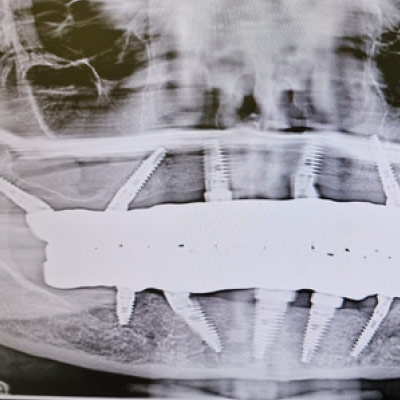

Full Arch Implant Rehabilitation

Questo corso ti prepara a gestire le riabilitazioni di una o entrambe le arcate su soli supporti implantari. Impariamo a gestire il paziente totalmente edentulo, parzialmente edentulo e quello con dentizione terminale.

All on x-procedures from A to Z.